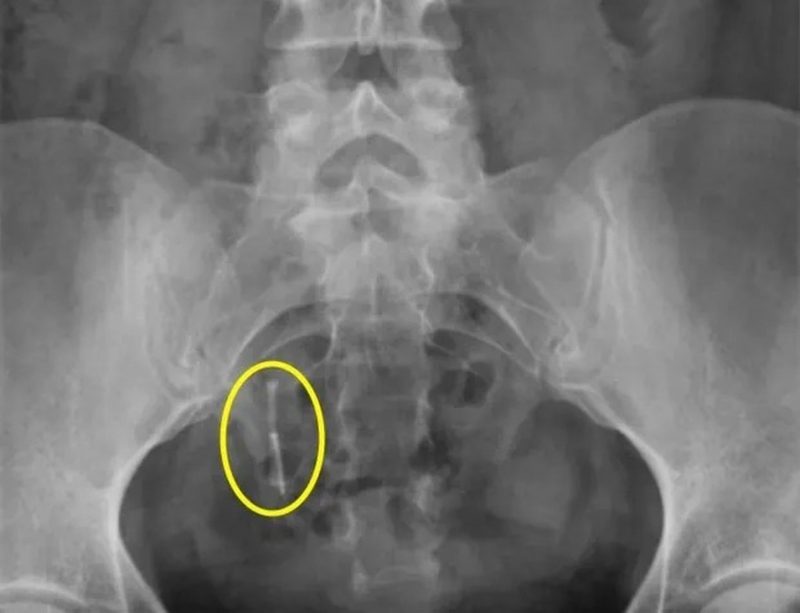

A americana Daniella Hampton, de 29 anos, encontrou por acaso seu “DIU” perdido há 12 anos, após um acidente de carro que a obrigou a fazer um raio-X. O dispositivo, que era para estar em seu útero, foi para o reto.

Raio-X de Daniella, que ficou com DIU 'perdido' dentro do corpoDIU se perdeu dentro do corpo de Daniella – Foto: Reprodução/Kennedy News and Media/ND

Ela colocou o DIU (Dispositivo Intrauterino) em 2009, mas seis semanas depois foi informada pelos médicos de que ele havia caído. A equipe afirmou que não conseguia sentir os fios do DIU e o ultrassom não mostrou nada.

Apenas em 2021, após Daniella sofrer um acidente de carro, um raio X revelou que o DIU havia perfurado seu útero e estava dentro de seu cólon.

No Facebook, a jovem de 29 anos compartilhou fotos de seus raios-X com a legenda “confiem em seus corpos, meninas. Eu sempre soube que ele estava dentro de mim, mas não conseguia provar”.